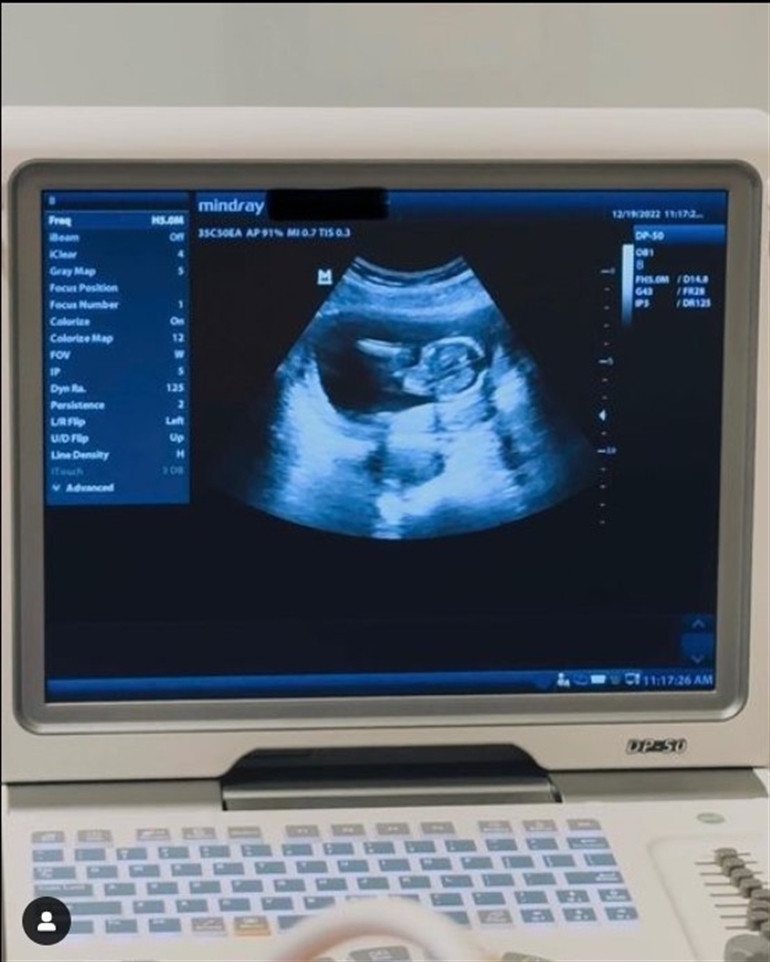

27 yaşındaki Ireland, 2022’nin hemen bitiminde hamile olduğunu Instagram hesabından paylaştığı bir ultrason fotoğrafıyla duyurmuş, hem hayranlarını hem de Baldwin ailesini sevindirmişti. Ireland’ın aktör babası Alec Baldwin, zor bir yıl geçirmiş; film çekerken yanlışlıkla ateş alan bir silahla filmin götüntü yönetmeni Halyna Hutchins'in ölümüne sebep olmuştu. Alec Baldwin ve eşi eşi Hilaria Baldwin, bu zorlu günlerden geçerken bir de çocuk sahibi oldular. Alec ve Hilaria Baldwin’in yedinci ve şimdilik son çocukları Ilaria Catalina Irena 22 Eylül’de dünyaya geldi. Henüz üç aylık bir kızı olan Alec Baldwin yılın sonunda bir de torun haberi aldı.